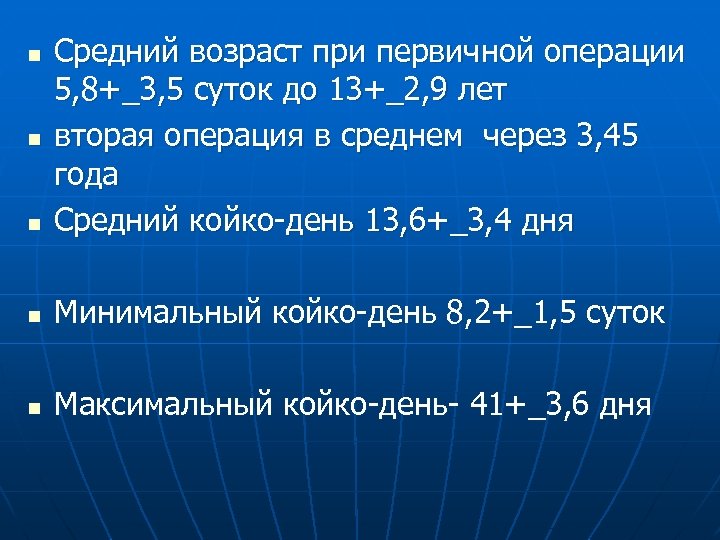

n Средний возраст при первичной операции 5, 8+_3, 5 суток до 13+_2, 9 лет вторая операция в среднем через 3, 45 года Средний койко-день 13, 6+_3, 4 дня n Минимальный койко-день 8, 2+_1, 5 суток n Максимальный койко-день- 41+_3, 6 дня n n